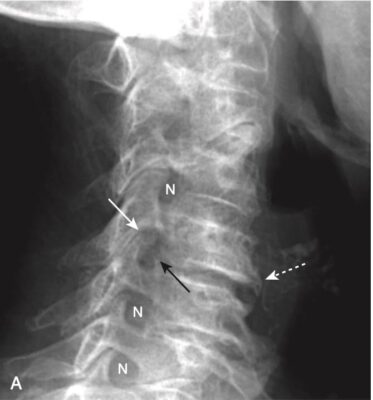

- Ở cột sống cổ, có ba đường cung song song tương xứng với nhau: (1) đường nối các đường giữa bản cung- mỏm gai, (2) đường nối mặt sau của các thân đốt sống, và (3) đường nối mặt trước của các thân đốt sống. Những thay đổi về ba đường cong song song này có thể chứng tỏ sự dịch chuyển ra phía trước hoặc phía sau của toàn bộ hoặc một phần thân đốt sống (Hình 2).

- Từ mức C3 đến mức L5, các thân đốt sống có hình gần như chữ nhật và có chiều cao trước sau bằng nhau.

- Các bề mặt của các thân đốt sống (end plate, bản tận) của các đốt sống tiếp giáp nhau gần như song song với nhau.

- Trong hình chiếu thẳng, mỗi thân đốt sống hiển thị hai cuống cung hình oval có thể nhìn thấy được ở hai bên của thân đốt sống. Các cuống cung của L5 thường rất khó nhìn thấy ngay cả ở những người bình thường, bởi vì độ ưỡn của cột sống thắt lưng (xem Hình 1, B).